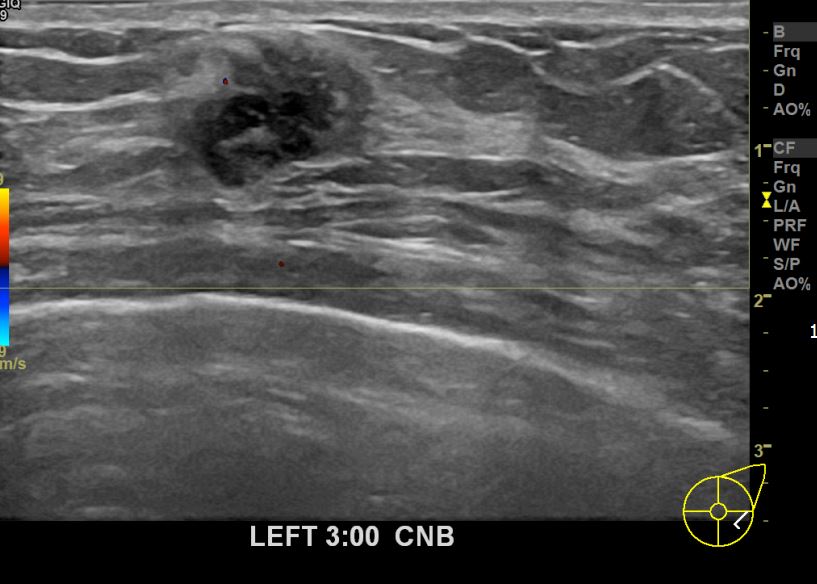

아산유외과개원후 663번째 유방암진단

상기환자 외부검사상 이상소견으로 내원하신 60대여성으로 좌측에 의심스러운혹 조직검사시행해 유방암 진단되었습니다